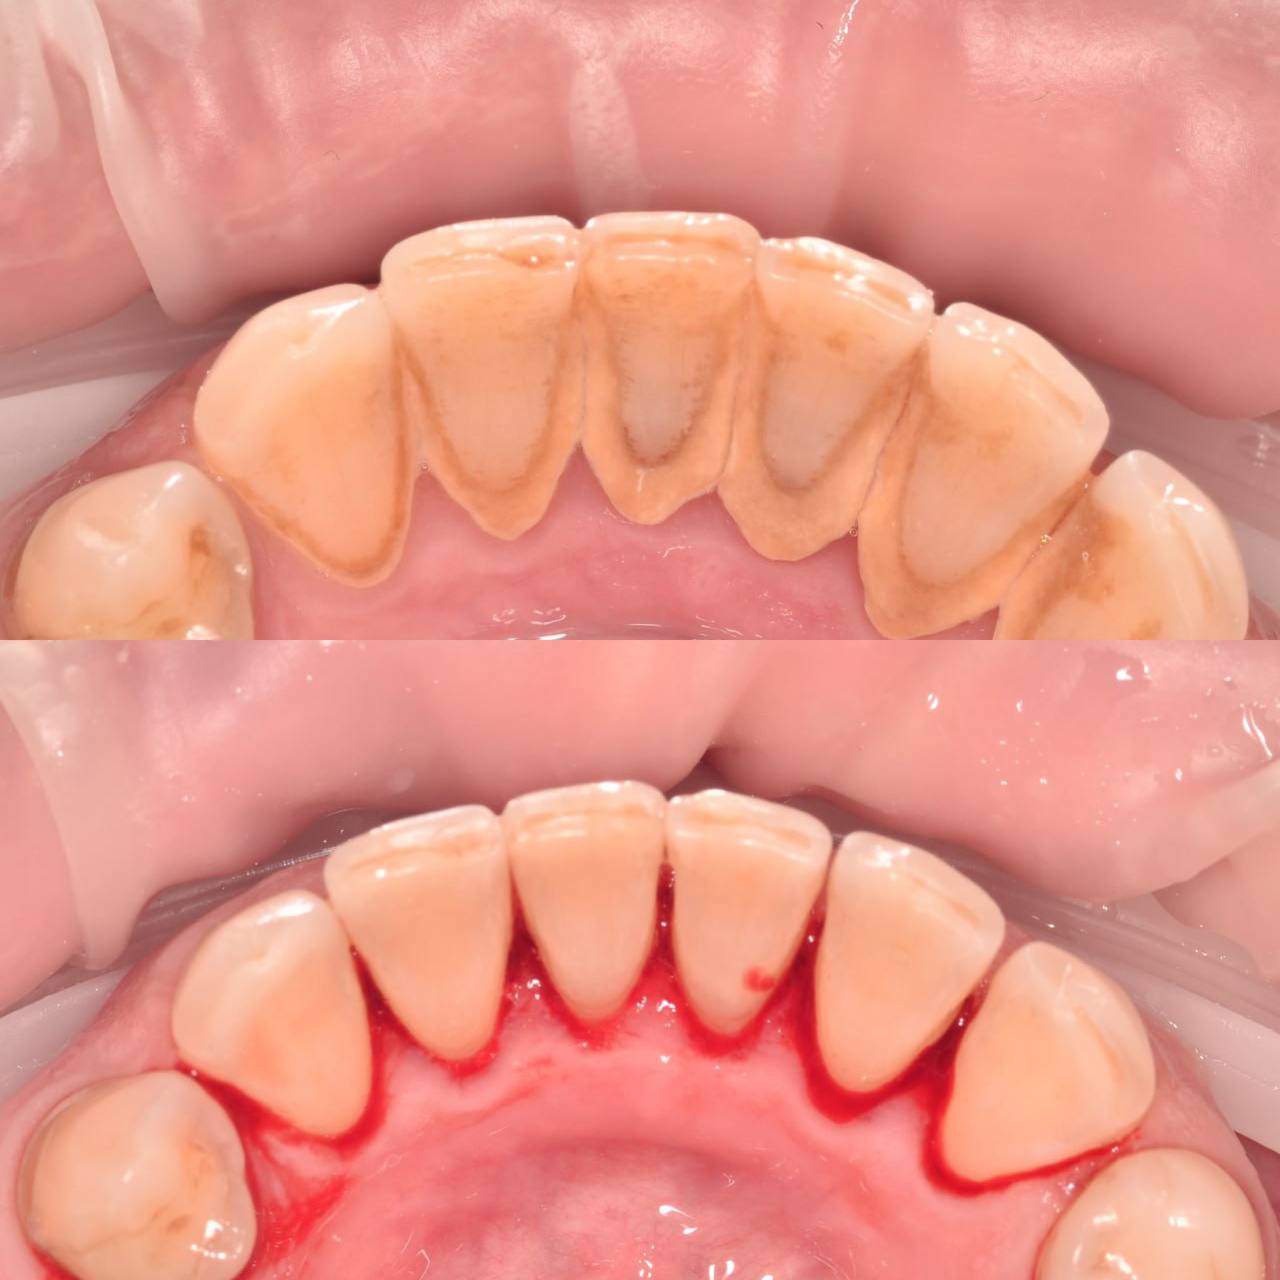

Даже если вы хорошо чистите зубы дома, на зубах со временем скапливается налет. А также на зубах есть труднодоступные места, которое вы не прочищаете. Поэтому нужно приходить на профгигиену в клинику не реже 1 раза в 6 месяцев. Очищение налета, удаление зубного камня, укрепление эмали — все это профессиональная гигиена. На сегодня это лучший способ защитить зубы от кариеса и сохранить десны здоровыми.

Процесс включает несколько этапов:

• Удаление зубного камня с помощью ультразвука;

• Очистка труднодоступных участков с использованием порошкового оборудования Air Flow;

• Полировка зубов специальными пастами, придающими эмали гладкость и блеск;

• Завершение процедуры нанесением реминерализующего состава для укрепления зубов.